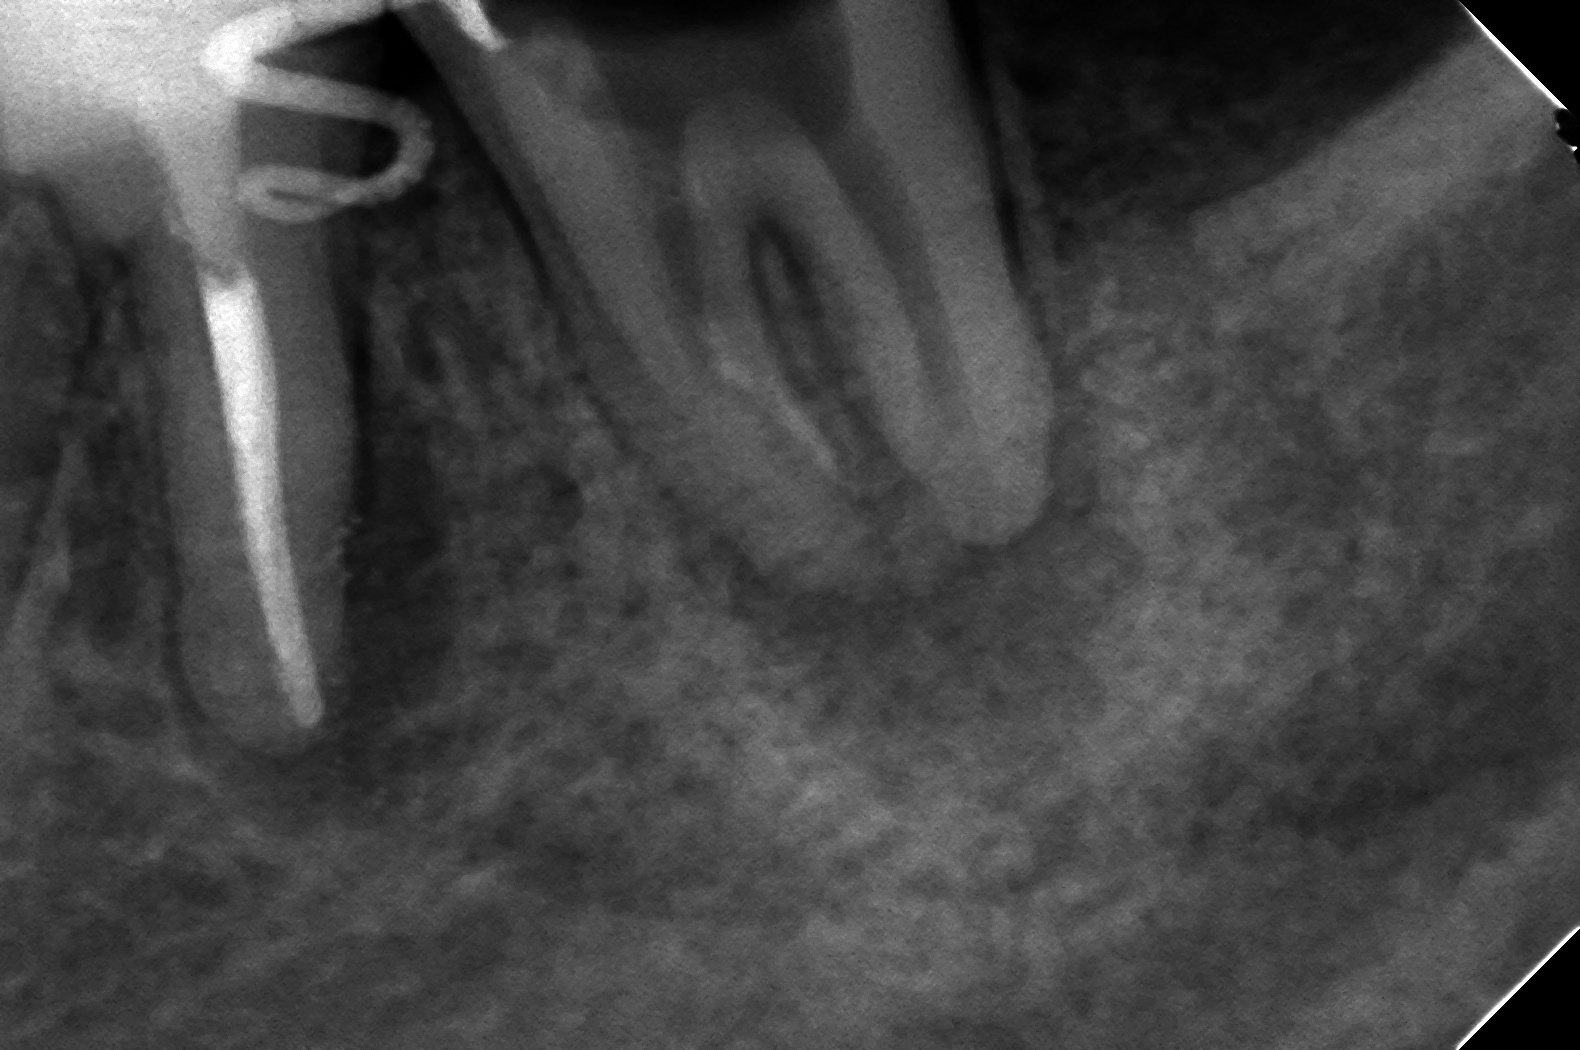

DB121237_151217204257(調整後)GPを除去して、壊死した歯髄を取り

DB121237_160107200332(調整後)垂直加圧しました

このような症例はメインポイントが入らないので、基本はコンテニアスウェーブは使えないですので、薄くSコンデンサーでシーラーを壁に塗布して、そーっとβを入れる感じでやってます。なので、GPもしくはシーラーが少し(結構)出てしまってます。

で、半年後

DB121237_161221191012(調整後)

綺麗に治りましたね!

飛び出てるのはいただけませんが、治れば良しです。